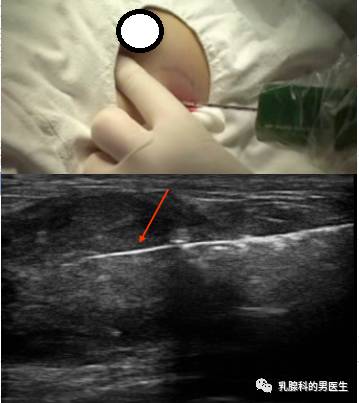

导读:还记得《乳腺科门诊日志(二)——乳腺检查的BI-RADS分类常识 一文中的C女士吗?今天让我们跟随她认识一下乳腺肿块空芯针穿刺活检,究竟是个啥?它的作用是什么?有何风险及并发症?

第二天,她拿着血常规及凝血功能的检查结果到了门诊穿刺室,血常规及凝血四项结果正常,没有凝血功能障碍,可以行穿刺。

L医生:说白了,就是在你的肿块周围打点麻药,在超声的引导下,用大概中性笔头粗细特殊穿刺针,在你的肿块上各个方向上随机的取一些“肉丝儿”下来,然后送到病理科,让病理医生在显微镜底下看看,它到底是好是坏。

空芯针穿刺活检就是用特殊器械,在超声或钼靶的引导下,对乳腺的可疑病灶穿刺取出部分腺体组织的检查。空心针活检取出的标本形状为条状,长度一般为2厘米。该技术采用专用穿刺粗针(国际号14-16G,针头外径2-4mm)。我们用14G的。